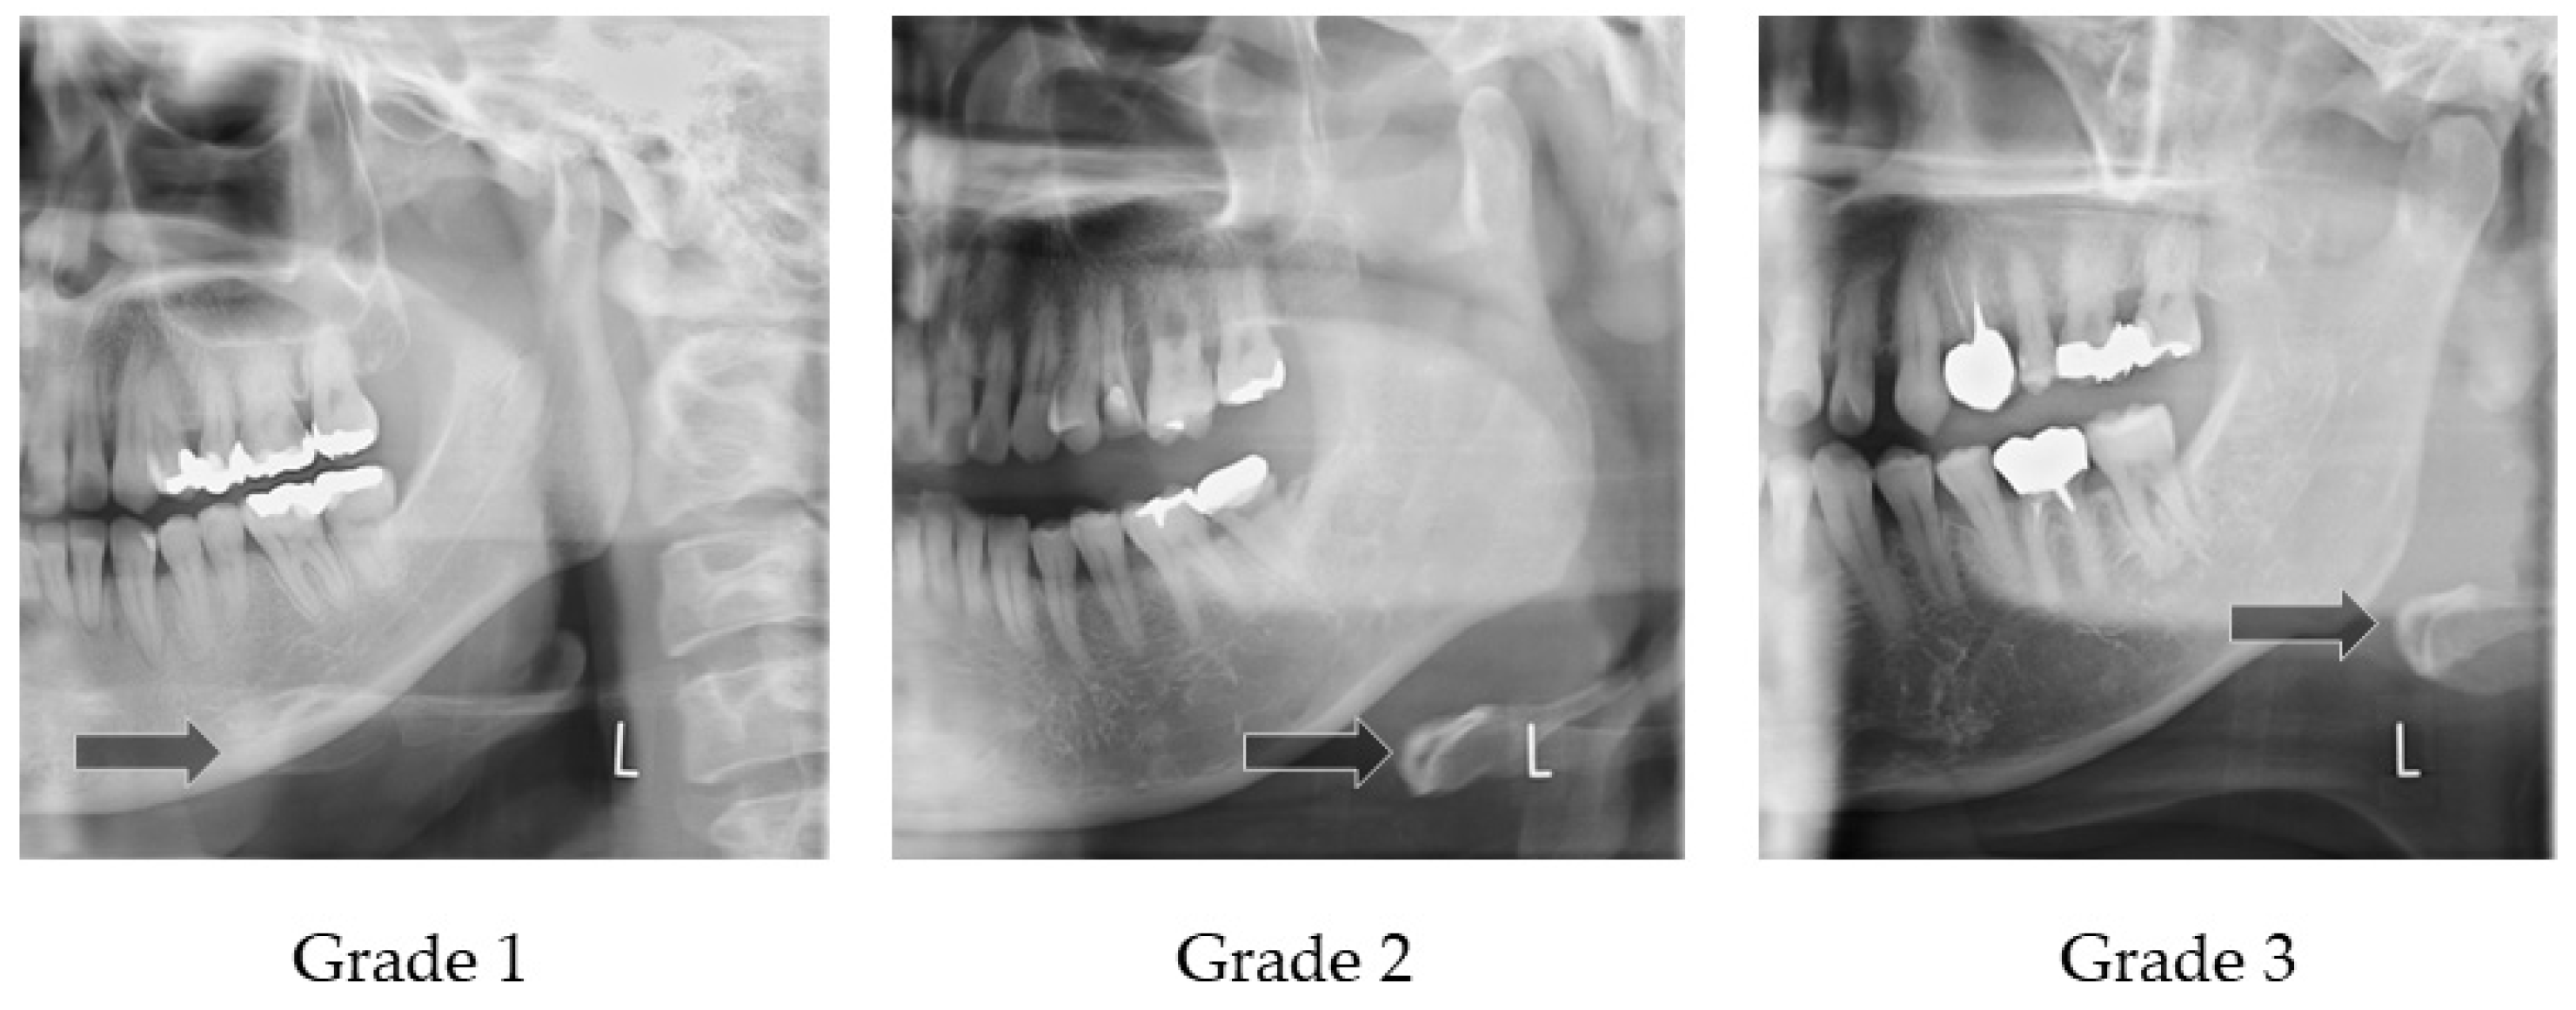

2.4.2. Horizontal Hyoid Bone Position

| Horizontal Hyoid Bone Position | Dysphagia (+) | Dysphagia (−) |

|---|---|---|

| Grade 1 | 5 | 9 |

| Grade 2 | 15 | 15 |

| Grade 3 | 4 | 3 |